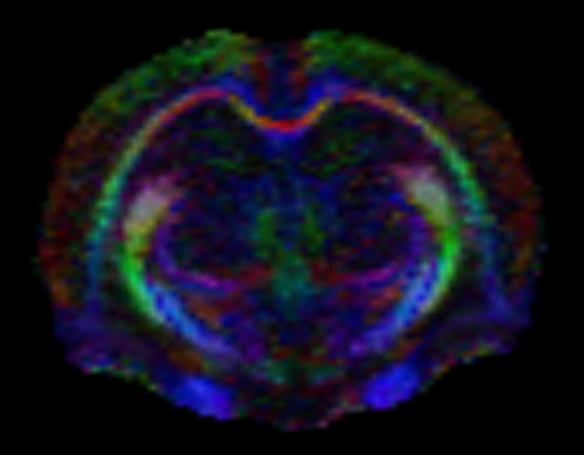

Yüksek manyetik alan gücü, daha küçük gantri çapı ve özelleşmiş hayvan sargıları (koil) sinyal-gürültü oranındaki iyileşmeye katkıda bulunur. SNR’daki bu iyileşme daha kaliteli görüntülere ve hassas patolojik değişimlere daha yüksek duyarlılığa olanak tanıyabilir. Daha yüksek SNR görüntüleme süresini kısaltabilir. Ayrıca fMRI, dinamik kontrast ve kardiyak sekanslar gibi yüksek zaman çözünürlüğünün önemli olduğu protokollerde avantajlıdır. Doğaları gereği düşük SNR sorunları olan difüzyon ağırlıklı görüntüleme ve difüzyon tensör görüntüleme gibi protokollerde de önemli iyileşmeler sağlar.

- Difüzyon tensör görüntüleme (DTI), traktografi

Difüzyon Görüntüleme Uygulamaları

Dokulardaki (örneğin beyin, karaciğer) difüzyon özellikleri difüzyon ağırlıklı görüntüleme sekansları ile değerlendirilebilmektedir. Buna ek olarak, beyindeki beyaz cevher yolaklarının fraksiyonel anizotropi (FA) gibi ayrıntılı özelliklerini değerlendirmeye ve traktografisine olanak tanıyan difüzyon tensor görüntüleme yapılabilmektedir.